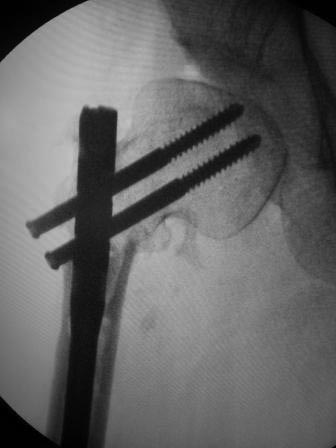

Уважаемые коллеги, обратилась девушка 1991г.р. 2 года назад оперирована в другой области по поводу диспластического коксоартроза ( похоже Мак Маррея, фиксация ЦИТО –Бакичарова), вот уже почти два года ходит с двумя костылями, наступать на ноги не может из-за боли, ногу активно поднять не может, активные движения в т/б суставе резко ограничены из-за боли, пассивные: 5/0/90гр, приведение - 20, отведение - 10гр, ротация-около -30, но болезненная. беспокоят боли в основном в обл ложного сустава, при движениях и пальпации в обл т/б сустава болей нет.

На Р-грамме, похоже, клинок пластини сломан, сращения нет.

Выраженность артроза относительная. Особенно учитывая минимальные субъективные ощущения пациентки в самом суставе, а это главный критерий при оценке необходимости эндопротезирования. Суставная поверхность, судя по рентгенологической картине имеет еще большой запас прочности. Налицо основная проблема - ложный сустав подвертельной области.Я попробовал бы реостеосинтез в положении coxa valga.Металлоконструкция зависит от возможностей вашей клиники. Long Gamma, как пример.

В проксимальном бедре в основном практикуется два вида остеотомии. Вальгусная - для лечения ложных суставов шейки бедра, где за счет увеличения длины абдукторов и перемещения оси конечности создаются благоприятные условия для сращения ложного сустава шейки. Создается максимум компрессии в зоне ложного сустава!

Пластина Бакычарова предназначена для лечения чрезвертельных переломов, где силовой вектор находится косо, и в такой конструкции невозможно создать поперечную компрессию. Поэтому перед выбором фиксатора необходимо тщательно обдумать, какой из фиксаторов подойдет для лечения ложного сустава. Иначе следующее осложнение может быть катастрофическим, потому что в результате осложнения можно потерять проксимальное бедро. А без проксимального бедра меняется механика тазобедренного сустава, которая может усложнить установку ножку протеза!

Предложенный БИОС с рассверливанием канала рекомендуется для лечения ложных суставов в диафизарной зоне! А здесь патология находится в межвертельной зоне и нет нужды устанавливать гвоздь. Любой гвоздь, включая цефаломедуллярные, не позволяет создать компрессию! Вместо БИОС 95 градусный Blade Plate, который минимизирует операцию и создаст компрессию в зоне!

Здесь вариант установки 95 градусной пластины при варусной остеотомии.

Уважаемые коллеги. Больная оперирована 06.03.15г клинок был сломан, и пока его с трудом удалили, от неполноценного вертела почти ничего не осталось, сломанный шуруп тоже удален, шейка совсем короткая, , ШДУ около 95гр, из-за сильного остеопороза при сверление в положении чуть вальгуса наружная стенка крошится , и еще что интересно при первой операции головка бедра оказалось фиксирована в положении ретроверсии примерно 10-15 гр.. и с трудом удалось выпрямить головку и шейку до 0 гр. , укорочение было чуть больше 1см , п/о -2см, пока фиксация - гипсовый сапожок с деротатором. Дальше как быть? Может временно фиксировать кокситной повязкой( канда каст)?